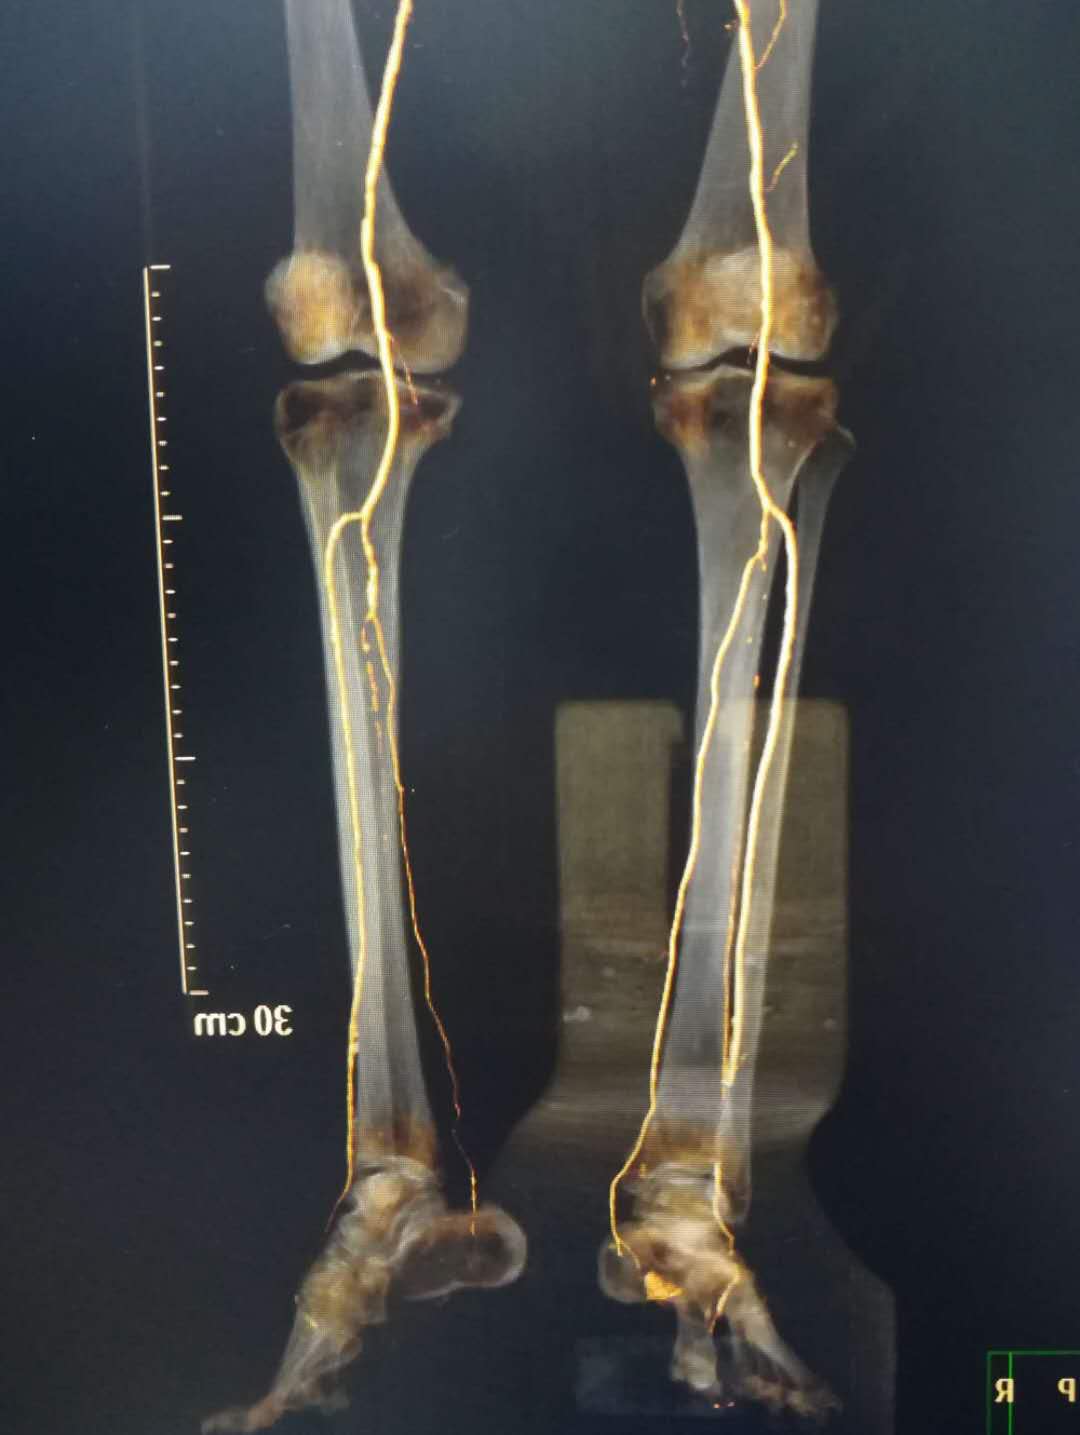

骨搬运手术前,微血管稀疏

搬运前血管稀疏